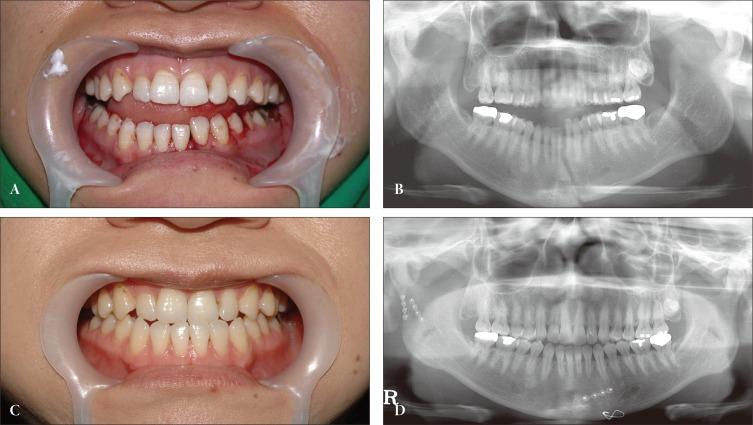

Maxillomandibular fixation (MMF) is usually used to treat double mandibular fractures. However, advancements in reduction and fixation techniques may allow recovery of the premorbid dental arch and occlusion without the use of MMF. We investigated whether anatomical reduction and microplate fixation without MMF could provide secure immobilization and correct occlusion in double mandibular fractures.

Thirty-four patients with double mandibular fractures were treated with open reduction and internal fixation without MMF. Both fracture sites were surgically treated. For bony fixations, we used microplates with or without wire. After reduction, each fracture site was fixed at two or three points to maintain anatomical alignment of the mandible. Interdental wiring was used to reduce the fracture at the superior border and to enhance stability for 6 weeks. Mouth opening was permitted immediately.

No major complications were observed, including infection, plate exposure, non-union, or significant malocclusion. Five patients experienced minor complications, among whom the only one patient experienced a persistant but mild malocclusion with no need for additional management.

This study showed that double mandibular fractures correction with two- or three-point fixation without MMF simplified the surgical procedure, increased patient comfort, and reduced complications, due to good stability and excellent adaptation.